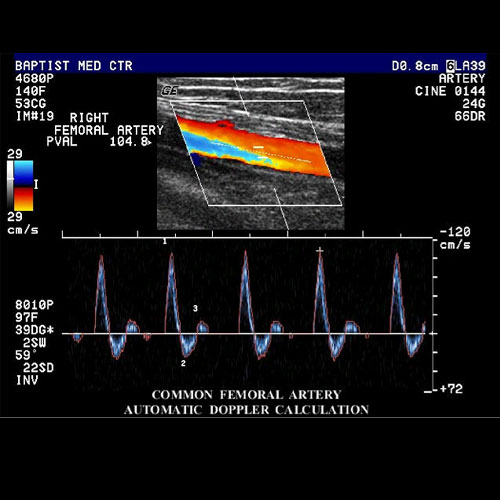

Ultrasound is used to examine the lower extremity arteries to provide an overview of the location, extent and severity of vascular disease. The ultrasound evaluation can be performed from the abdominal aorta through the tibial vessels and extended into the foot in order to facilitate clinical management decisions.

A highly trained technician will use the probe to evaluate the arteries from your groin to your ankles at several different sites.